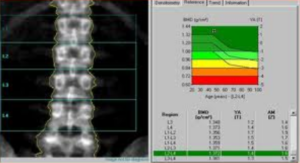

Vertebral Fracture Assessment (VFA/MXA)

La VFA viene eseguita utilizzando la tecnologia Dual-energy X-ray Absorptiometry (DEXA), la stessa impiegata per la misurazione della densità ossea. Questa tecnica ha guadagnato rapidamente terreno nella pratica clinica grazie alla sua praticità e sicurezza. Molti sistemi moderni utilizzano una tecnologia a raggio a ventaglio (fan-beam) con un braccio rotante che acquisisce l’immagine laterale del paziente in posizione supina, eliminando gran parte delle distorsioni geometriche tipiche della radiologia conica.6

- convenienza diagnostica: consente di valutare BMD, TBS e morfometria in un’unica sessione, fornendo un quadro clinico immediato;

La misurazione quantitativa computerizzata automatizza questo processo posizionando sei punti (reperi) su ogni corpo vertebrale, calcolando istantaneamente i rapporti tra le altezze anteriore, centrale e posteriore.

Sebbene la misurazione automatica sia rapida, la supervisione del radiologo è indispensabile per confermare la natura osteoporotica della deformità e non confonderla con varianti anatomiche o processi degenerativi.